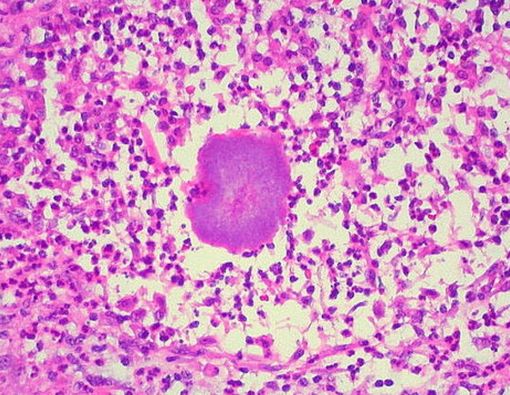

Mycetoma merupakan penyakit yang disebabkan oleh jenis bakteri atau jamur tertentu yang ditemukan di tanah atau air. Bakteri dan jamur ini masuk ke tubuh melalui luka pada kulit, sering kali lewat kaki.

Pada penyakit mycetoma, infeksi menyerang kulit dan jaringan subkutan. Kondisi ini dapat memengaruhi otot, tulang, tendon, dan sendi. Meski begitu, mycetoma tidak menular dari satu orang ke orang lain.

- Eumycetoma (akibat jamur).

- Actinomycetoma (akibat bakteri).